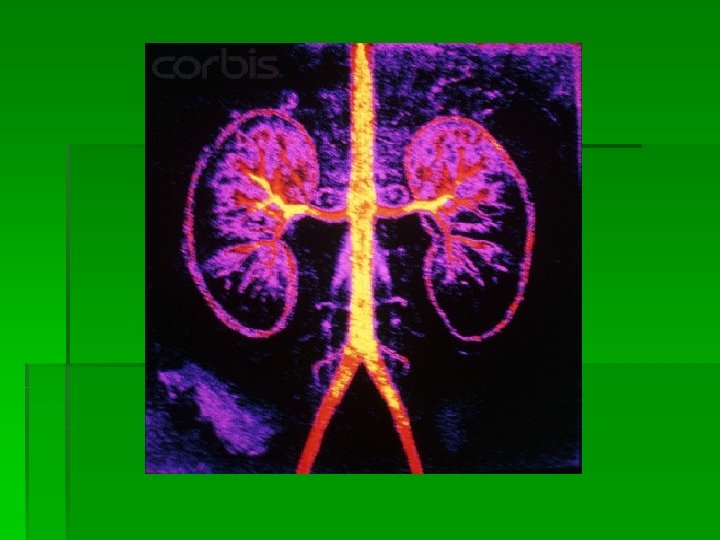

Kidneys § Paired § Located retroperitoneally on the posterior wall of the abdomen from T 12 -L 3 § The average adult kidney weighs 4. 5 oz § The right kidney sits lower in the abdomen due to liver placement § An adrenal gland sits on top of each kidney

Kidney Anatomy § Each kidney has two parts § The renal medulla is the inner portion § consists of renal pyramids which are collecting ducts that drain into renal pelvis § Once urine leaves the renal pelvis the composition or amount of urine does not change § The Cortex is the outer portion § contains nephrons